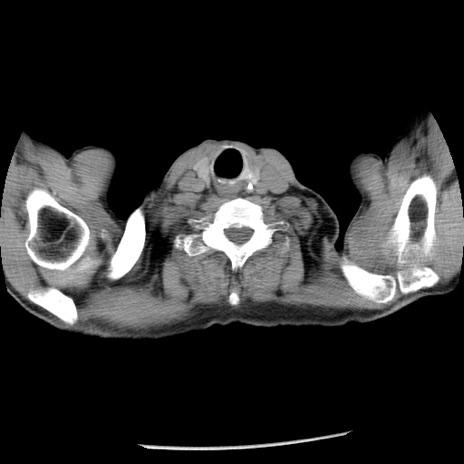

症例26(横断像)

【症例】80歳代男性

【主訴】嘔吐

【現病歴】昨晩2回嘔吐あり、今朝になっても嘔吐あり。来院。

【既往歴】胃潰瘍

【身体所見】意識清明、BT 37.6℃、BP 166/95mmHg、HR 100bpm、SpO2 97%、腹部:平坦・軟、腸蠕動音聴取良好、圧痛なし。

【データ】WBC 21900、CRP 1.46